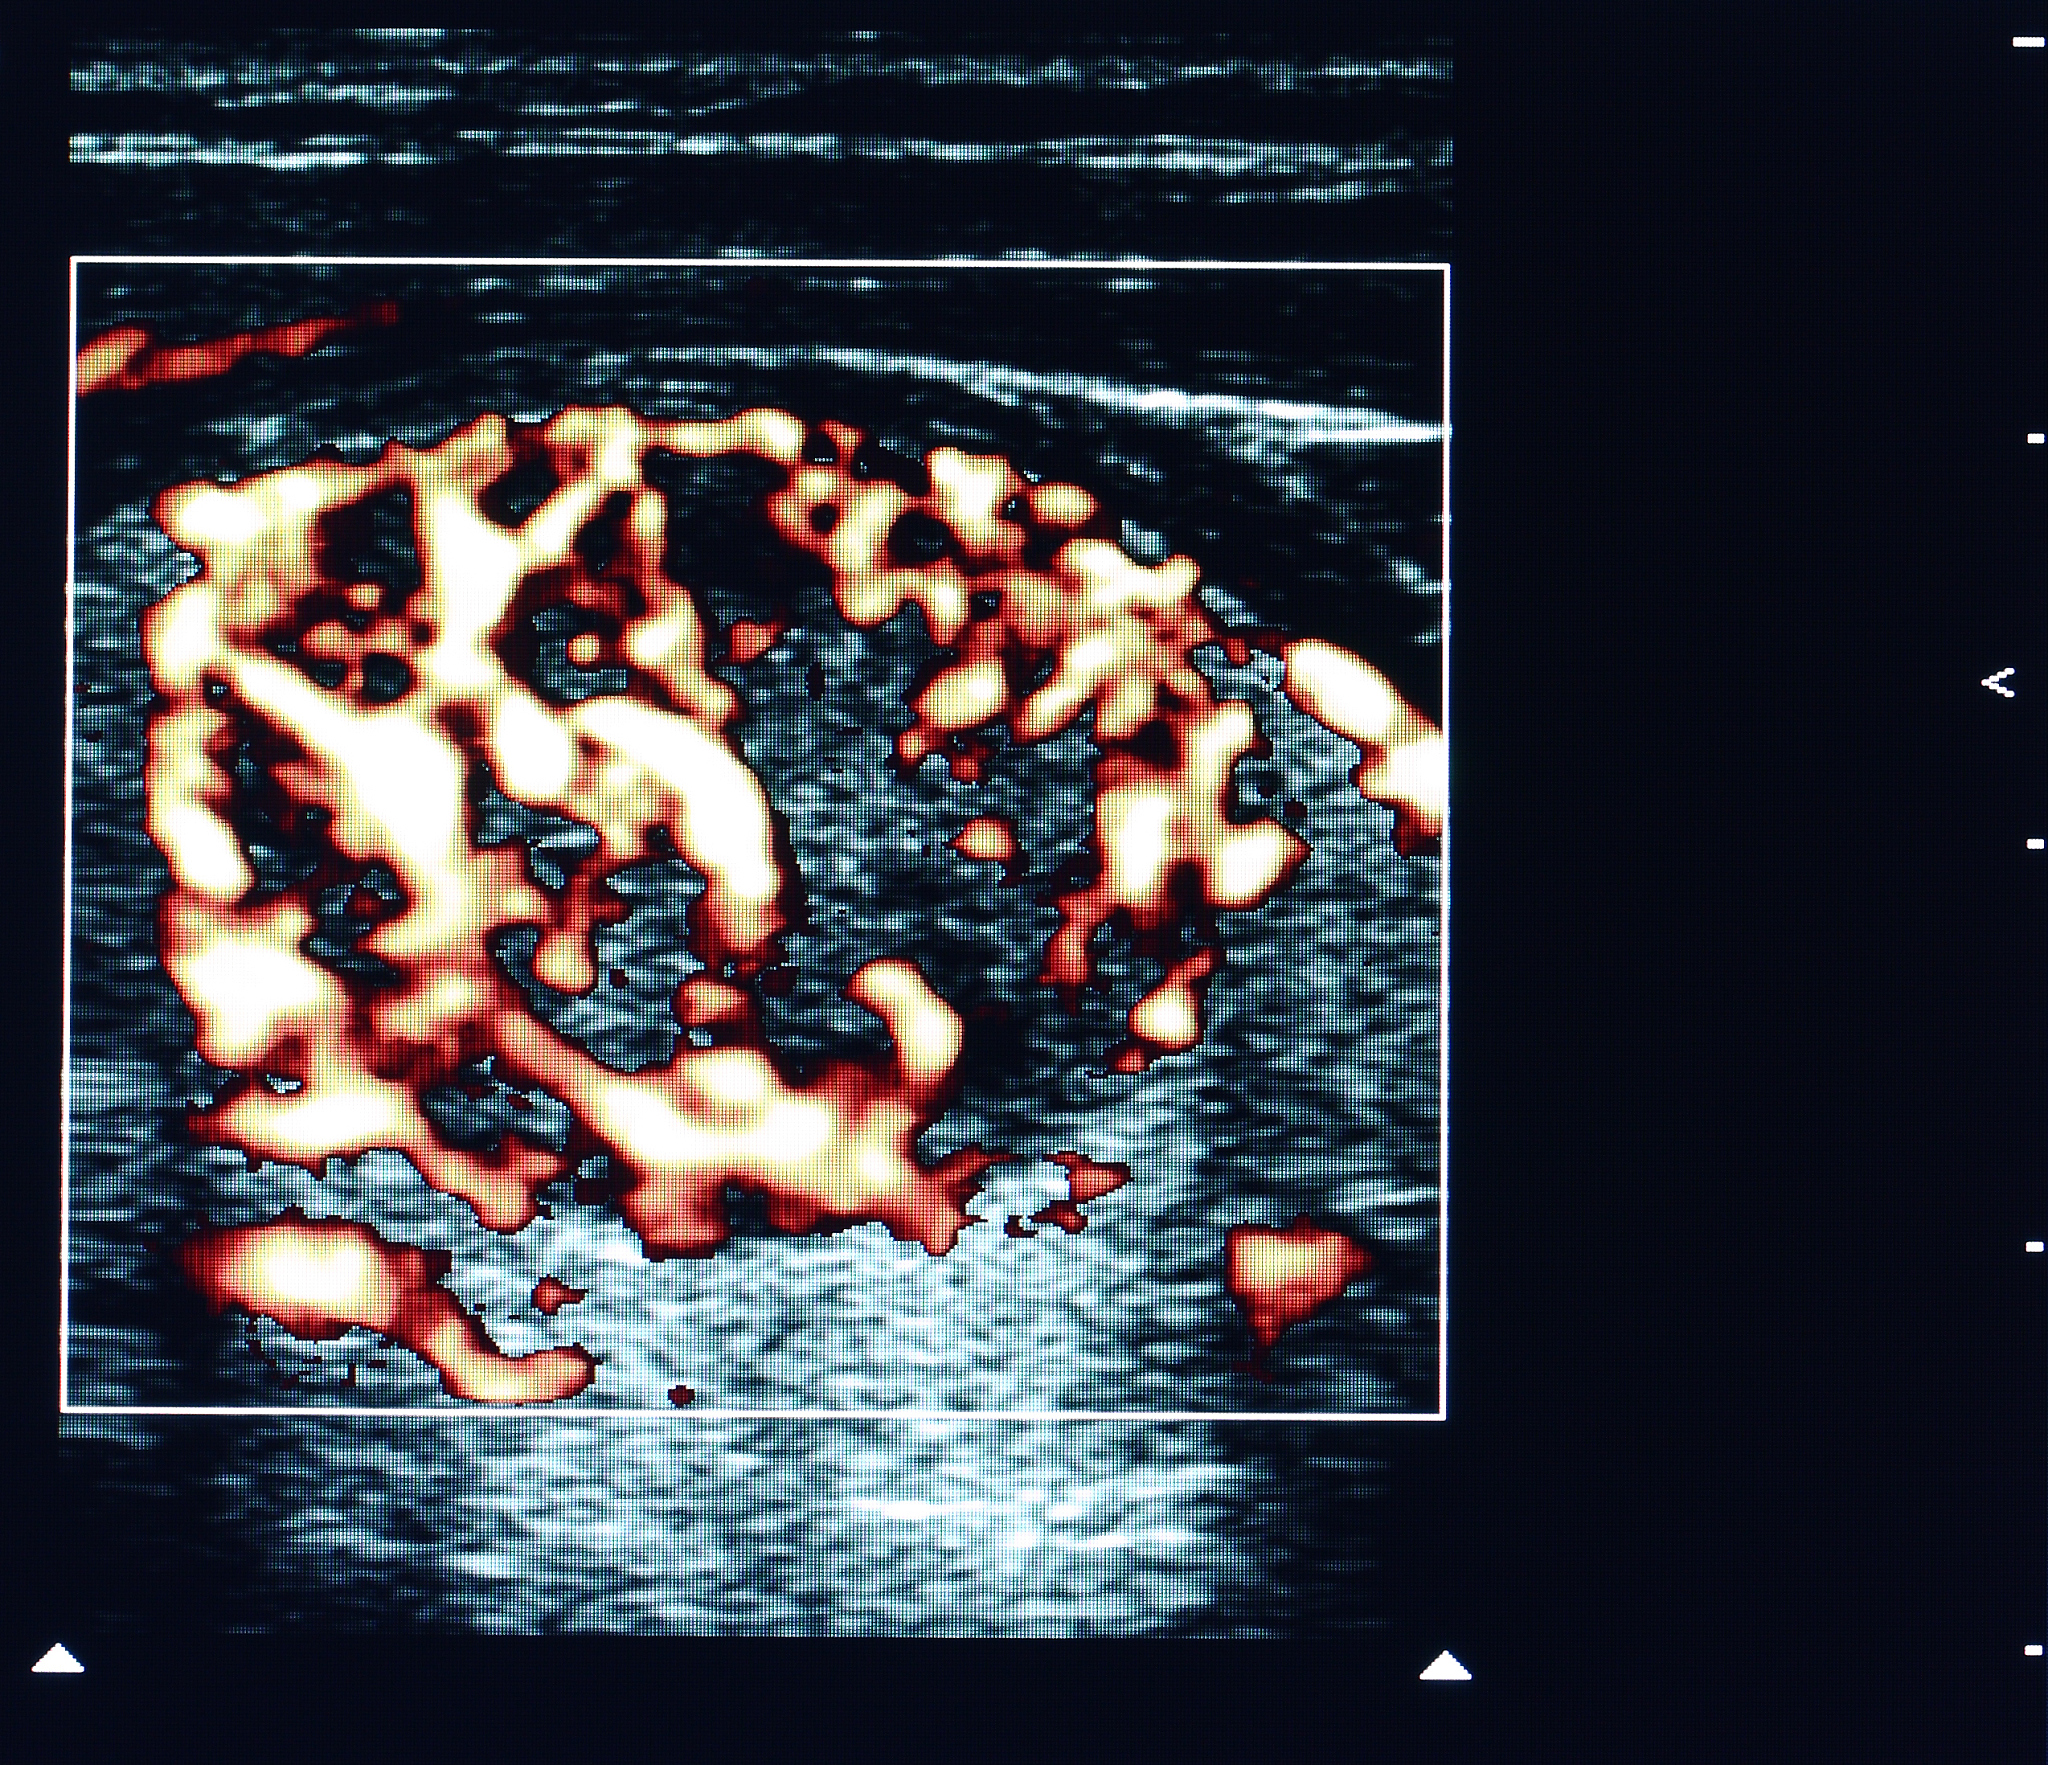

增强超声在斑块成像中的优势:对比CTA和DSA

在这种情况下,与CTA和DSA相比,增强超声在可视化'斑块内新生血管化'和'斑块内微溃疡'方面具有显著的优势。此外,增强超声因其简单便捷的操作、实时监测能力、非侵入性、无辐射暴露、无肾毒性以及适用于床边检查而脱颖而出。